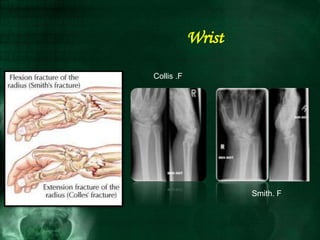

Wrist

Smith. F

Collis .F